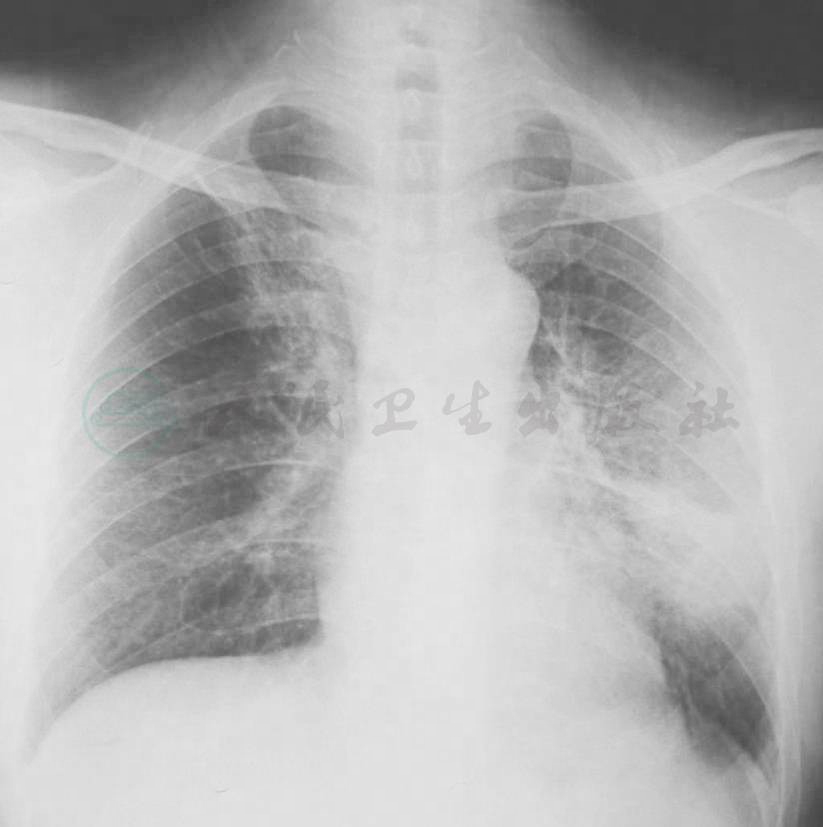

系列胸部影像学检查表现见图1~图5。

图2 X线胸片(2009-11-11)

X线胸片示左下叶斑片影较前明显吸收

图4 X线胸片表现(2009-11-17)

X线胸片示双肺多发结节影

3.胸部影像学特点为病初见左下肺斑片影,莫西沙星治疗后肺部阴影吸收,停用后肺部阴影短期内再次增多。

患者此次为急性起病,病初为中-高热,莫西沙星短期治疗一度有效,病情(临床表现和肺部阴影)得以缓解,但停药后短期内再次发热、肺部阴影再现(绝大多数肺部阴影在原有病变基础上增大),首先考虑为感染性疾病所致的可能性大,并且结合莫西沙星的治疗作用,考虑为莫西沙星能覆盖/部分覆盖的病原体(包括多种常见可导致社区获得性肺炎的病原体,如肺炎链球菌、苯唑西林敏感金黄色葡萄球菌、支原体、军团菌等)。鉴于患者病情加重后,胸部CT表现为在原来病变基础上出现结节、空洞,重点考虑金葡菌感染的可能,同时须鉴别由于库欣综合征、继发性糖尿病血糖水平控制差,其他多种病原(如结核分枝杆菌、非结核分枝杆菌、诺卡菌等)导致的机会感染,尚需进一步病原学检查结果证实。其次,还需要考虑非感染性疾病,尤其是肺部肿瘤性疾病。患者有库欣综合征,需要警惕神经内分泌肿瘤可能。由于患者肺部阴影在抗感染治疗后缩小,停药后在短期内又明显增大、增多,不是肿瘤性疾病常见的表现,故可排除。此外,虽然抗中性粒细胞胞质抗体(ANCA)相关性血管炎也可以表现为肺内多发结节、空洞影,但抗感染药物无效,与本病例病情变化情况不符。